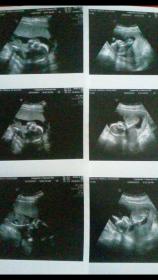

Attachment 36356

Heres baby at 13 weeks